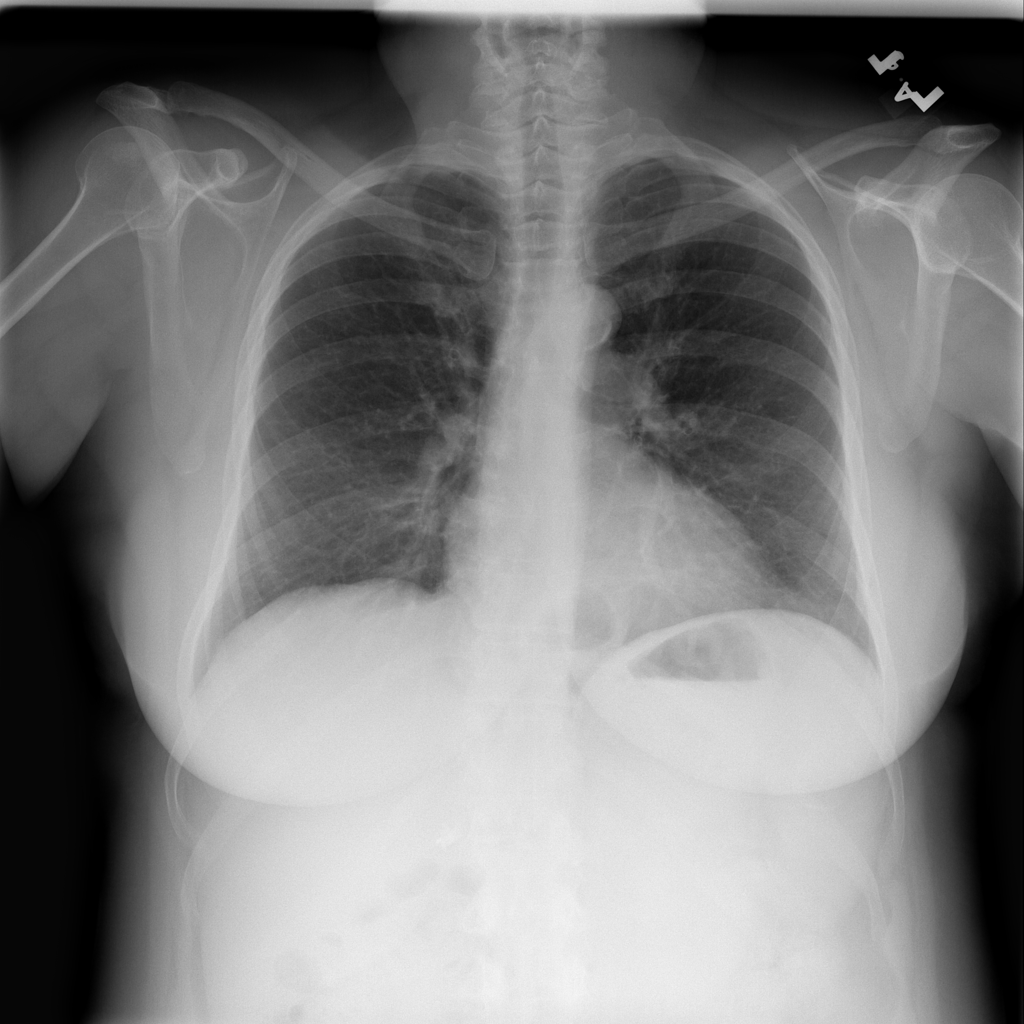

PAT-C048 · IMG-001Hernia

PAT-C048 · IMG-001

PA